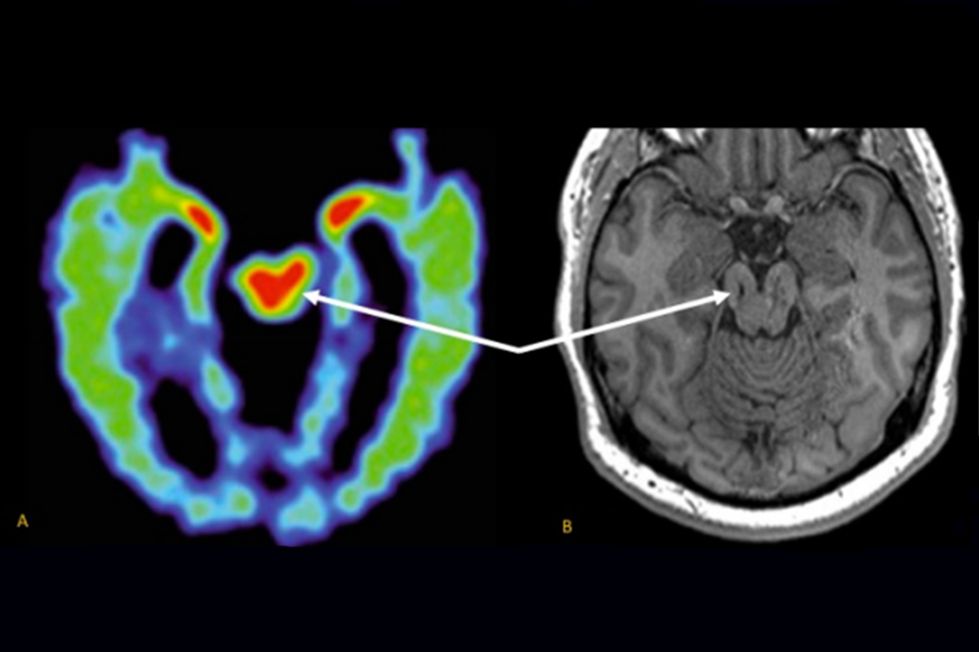

El 25 de febrero de 2026, la revista Neurology publicó un avance significativo en la búsqueda de biomarcadores in vivo para enfermedades neurodegenerativas vinculadas al deporte. Bajo el marco del proyecto DIAGNOSE CTE (Diagnostics, Imaging, and Genetics Network for the Objective Study and Evaluation of CTE), investigadores de la Universidad de Florida y la Universidad de Boston han logrado observar la huella del trauma en el cerebro vivo, identificando la inflamación como un puente biológico hacia la destrucción estructural.

En su obra “Textura del sistema nervioso del hombre y los vertebrados”, Cajal detalló la arquitectura del asta de Amón y sus conexiones con una devoción casi mística. En 2026, la imagen por tensor de difusión (DTI) nos permite evaluar la integridad de estos circuitos mediante la anisotropía fraccional (FA) y la difusividad media (MD).

Los hallazgos indican que la inflamación explica una parte sustancial de la varianza en la degradación de la materia blanca límbica (3% para IL-6 y 5% para TNF-α). Aunque estas cifras son modestas, resultan estadísticamente fundamentales en la cascada degenerativa: la inflamación daña primero la estructura (tractos como el fórnix y el cíngulo) y esta alteración estructural es la que finalmente aniquila la memoria. Es imperativo notar que estas asociaciones fueron considerablemente más fuertes en el subgrupo de atletas con “CTE probable”, aquellos que sufren el síndrome de encefalopatía traumática (TES) con mayor severidad.